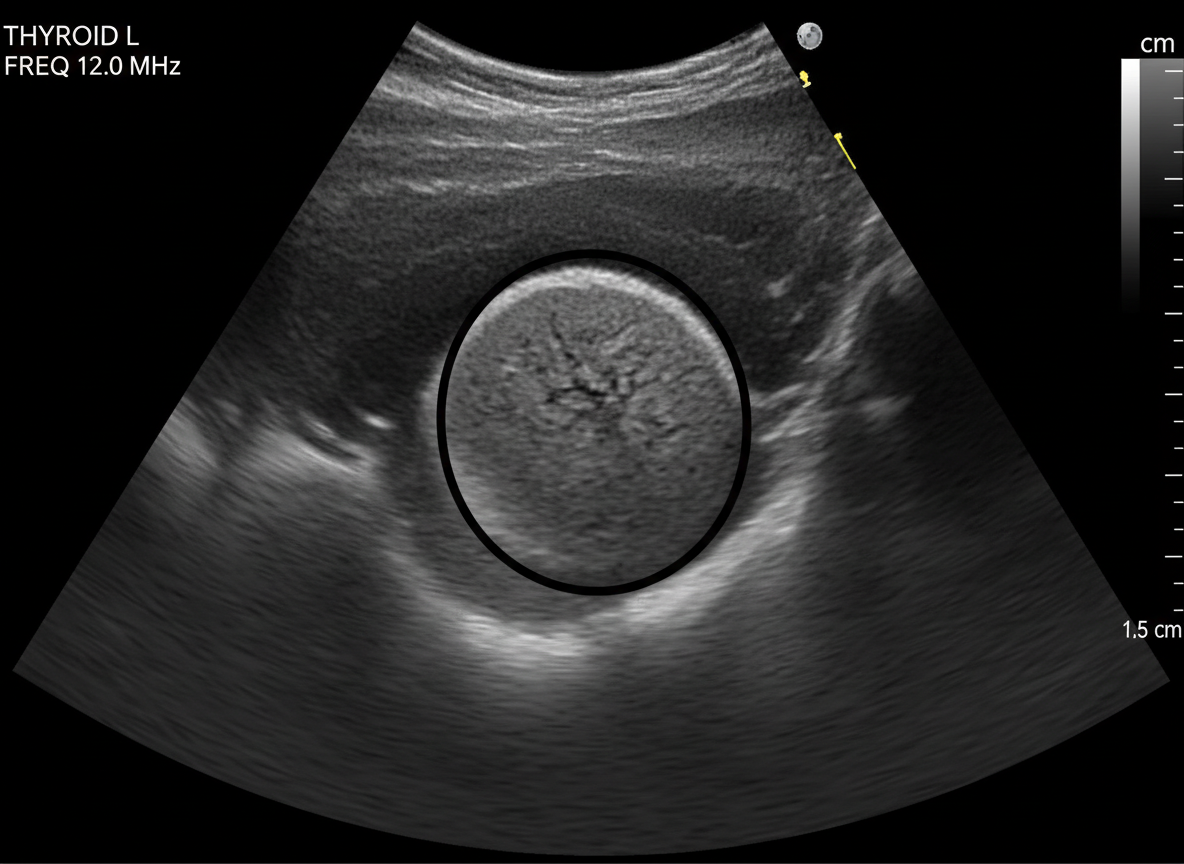

- 갑상선 초음파: 갑상선 내부의 결절 유무, 크기, 모양, 경계 등을 아주 자세히 확인할 수 있는 검사예요.비교적 간단하고 통증 없이 진행돼서 많이 사용된답니다.암이 의심되는 결절이 발견되면 다음 단계로 넘어가죠.